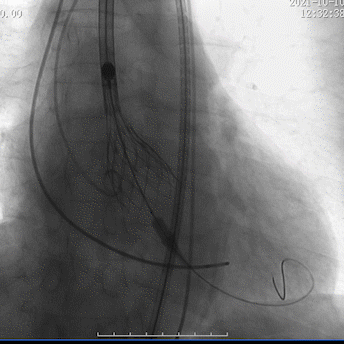

经过反复评估和研讨后,考虑国内首创的电动可回收输送系统, 以及VitaFlow Liberty™瓣膜的长裙边能提供足够的锚定空间,比较合适类似病例,可以实现快速稳定且较为精准的释放、回收、及瓣膜锚定。最终决定右股动脉入路、植入30型号瓣膜,监护麻醉,经右侧股动脉行TAVR,临时起搏器起搏,植入VitaFlow 30瓣膜。

瓣膜回收调整位置

瓣膜再定位

瓣膜植入较深

瓣膜再回收调整

瓣膜释放至可回收极限处造影

瓣膜完全释放后造影

在多学科协作下,高州市人民医院心脏外科陈凯明、刘浪教授团队完成首例VitaFlow Liberty™主动脉瓣置换。经过2个小时紧张有序的操作,术中借助VitaFlow Liberty™的可回收技术,帮助瓣膜精准定位植入,术后造影检查和心脏彩超评估瓣膜形态活动良好,没有瓣周漏。手术取得圆满成功,患者心功能改善显著,次日转回普通病房。